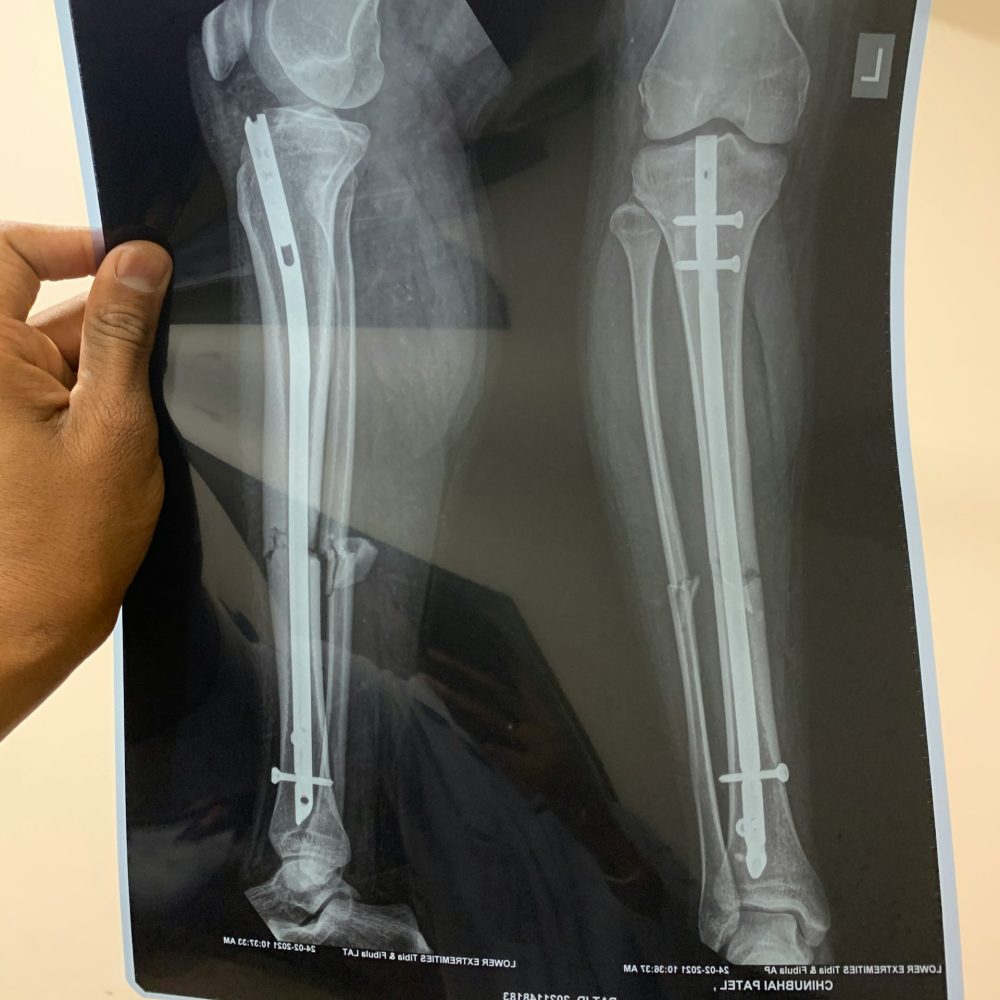

Tokom operacije hirurg pravi mali rez na butini i pažljivo prelomi butnu kost pod potpunom kontrolom i uz pomoć rendgenskog navođenja. U kost se ugrađuje intramedularna šipka koja drži prelom stabilnim i omogućava postepeno razdvajanje krajeva kosti. Pacijent zatim pomoću specijalnog mehanizma svakodnevno produžava kost za nekoliko milimetara, čime se stimuliše stvaranje nove kosti i mekog tkiva. Zahvat je precizan i izvodi se u strogo kontrolisanim bolničkim uslovima.

Nekada su se koristile spoljašnje fiksacije poput Ilizarov aparata, koje su bile bolne, spore i zahtevale mesece nošenja metalnih prstenova. Danas su dostupni moderni intramedularni sistemi – teleskopske šipke koje se ugrađuju unutar kosti i koje omogućavaju precizno, postepeno i komforno produženje. Nove tehnologije skraćuju vreme rehabilitacije, smanjuju rizik od infekcija i omogućavaju ranije vraćanje svakodnevnim aktivnostima, uz znatno bolje estetske rezultate.

Intramedullary Limb Lengthening ili Internal Nail Limb Lengthening Moderna metoda koja koristi teleskopsku šipku ugrađenu u kost (npr. Precice, Fitbone, druge varijante).

Intramedularno produženje se najčešće radi na butnoj kosti (femur), jer ona ima veliku medularnu šupljinu i dobro zarasta. Po potrebi, produženje je moguće uraditi i na potkolenici (tibia), što je češće kada pacijent želi dodatnih nekoliko centimetara ili kada proporcije nogu to zahtevaju. Produženje na tibiji može biti sporije i zahtevnije za rehabilitaciju, pa se ponekad kombinuje sa femoralnim produženjem u dve faze.